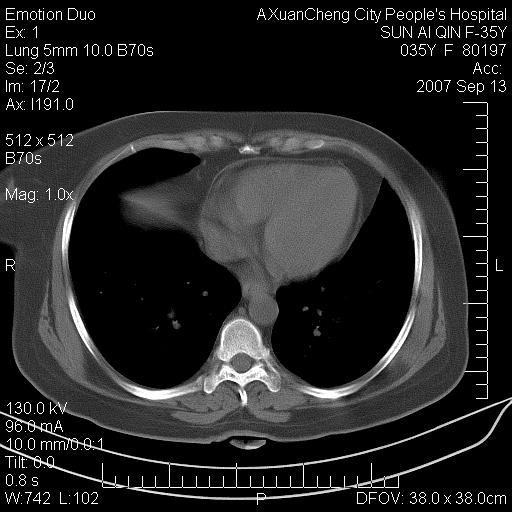

以下是引用天南地北在2007-9-13 13:43:00的发言:[br]考虑双肺、肺门侵润

以下是引用ydx_74在2007-9-13 15:42:00的发言:[br]仅看片,考虑右上肺癌并双肺转移,结合病史,考虑肺门、肺内淋巴侵润

以下是引用同在2007-9-13 15:08:00的发言:[br]支持肺门及双肺侵润.